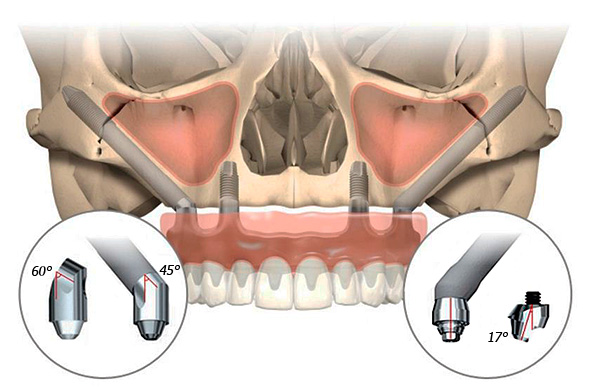

Portanto, as diferenças fundamentais entre a tecnologia de próteses dentárias All-on-4 são as seguintes:

- Apenas 4 implantes dentários são utilizados para próteses de dentição completa;

- 2 implantes são fixados em ângulo nas áreas laterais (entre o quinto e o sexto dente); 2 outros - verticalmente no lugar dos dentes da frente;

- Os implantes são construções clássicas de duas partes, mas é usado um pilar de várias unidades (angular), destinado a ser usado com uma inclinação específica dos implantes. Ou seja, o próprio pilar após a fixação adquire uma posição estritamente vertical;

O conceito implica o uso de apenas 4 implantes (com a abordagem clássica, eles exigem pelo menos 8 a 10 por linha). Dois estão ligados na região dos dentes anteriores, os outros dois na região lateral. E eles são fixados em um ângulo de até 45º.

A instalação inclinada de implantes laterais possibilita sua implantação, contornando estruturas anatômicas importantes, por exemplo, nervos da mandíbula, seios da face. Além disso, é possível colocar os implantes de maneira mais uniforme ao longo da crista alveolar e distribuir de maneira ideal a carga sobre eles. A inclinação dos “parafusos” laterais também permite aumentar a área de contato entre o implante e o osso, o que cria um suporte completo para a prótese.

O pilar é fixado na parte superior do implante. Para implantes inclinados, os pilares inclinados (unidades múltiplas) também são selecionados. Por esse motivo, a posição das pontas dos implantes acima da gengiva é nivelada e a prótese é fixada estritamente diretamente, sem perturbar a oclusão e oclusão do paciente.